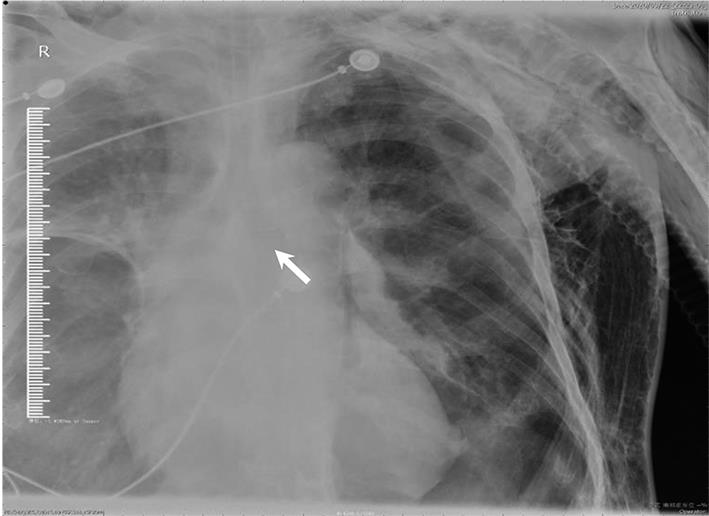

• 基于宏基因组二代测序诊断15例鹦鹉热衣原体肺炎临床特征与诊治分析

2023, 48(6):715-720. DOI: 10.13406/j.cnki.cyxb.003248

摘要 (49) HTML (29) PDF 858.28 K (202) 评论 (0) 收藏

摘要:目的 探讨和分析少见鹦鹉热衣原体肺炎的临床特征、诊治及预后,以期提升临床相关学科领域对该病的认识。方法 回顾性研究赣南医学院第一附属医院2017年1月至2022年12月确诊的15例鹦鹉热衣原体肺炎患者的临床资料,总结并分析该病的临床特征、诊断与鉴别要点,同时检索国内外文献资料对鹦鹉热衣原体肺炎的最新诊疗进展予以系统性讨论。结果 纳入本研究的15例鹦鹉热衣原体肺炎患者中,男性10例(66.67%),女性5例(33.33%),年龄62(32~79)岁,禽类接触史14例(93.33%),基础疾病史8例(53.3%),转化为重症肺炎5例(33.33%)。15例患者中,白细胞计数(white blood cell count,WBC)正常8例(53.3%),WBC升高5例(33.3%),WBC减低2例(13.3%);血红蛋白(hemoglobin,HGB)正常9例(60.0%),减低6例(40.0%);中性粒细胞百分比(neutrophils,NE)升高13例(86.7%);所有患者(100.0%)C反应蛋白(C-reactive protein,CRP)均显著升高;13例(86.67%)患者降钙素原(procalcitonin,PCT)升高;12例(80.0%)患者乳酸脱氢酶(lactate dehydrogenase,LDH)升高;11例(73.33%)肝功能异常;8例(53.33%)肾功能异常;6例(40.0%)凝血功能异常;13例(86.7%)电解质紊乱。此外,11例(73.33%)患者动脉血气分析显示不同程度血氧分压降低,8例(53.33%)氧合指数(oxygenation index,OI)低于300 mmHg,4例(26.67%)患者无明显呼吸困难,未进行动脉血气分析检查。本研究所有患者均已完善经支气管镜检查,并获取支气管肺泡灌洗液(bronchoalverolar lavage fluid,BALF)行宏基因组二代测序(metagenomic next-generation sequencing,mNGS)检测,检出的病原体除鹦鹉热衣原体外,所有患者均合并多种病原体感染。15例患者均已完善肺部电子计算机断层扫描(computed tomography,CT)等影像学检查,单侧肺部实变7例(46.67%),双侧实变8例(53.33%);9例(60.0%)患者伴有胸腔积液,部分患者可以表现出多种影像学表现,包括实变影、磨玻璃影、团块样实变影、反晕征、纵隔和肺门淋巴结肿大等。15例鹦鹉热衣原体肺炎患者在确诊后均予规范抗感染治疗,其中5例重症肺炎患者中2例患者予体外膜肺氧合(extracorporeal membrane oxygenation,ECMO)辅助治疗,所有患者均未见治疗相关不良反应或不良事件,平均住院日为13.9 d。本研究所有患者未见死亡,均好转出院。结论 鹦鹉热衣原体肺炎临床特征及表现缺乏特异性,易出现重症化,经支气管肺泡灌洗液予mNGS检测可精准确诊,早期予四环素类及喹诺酮类抗生素可最大程度改善患者预后。